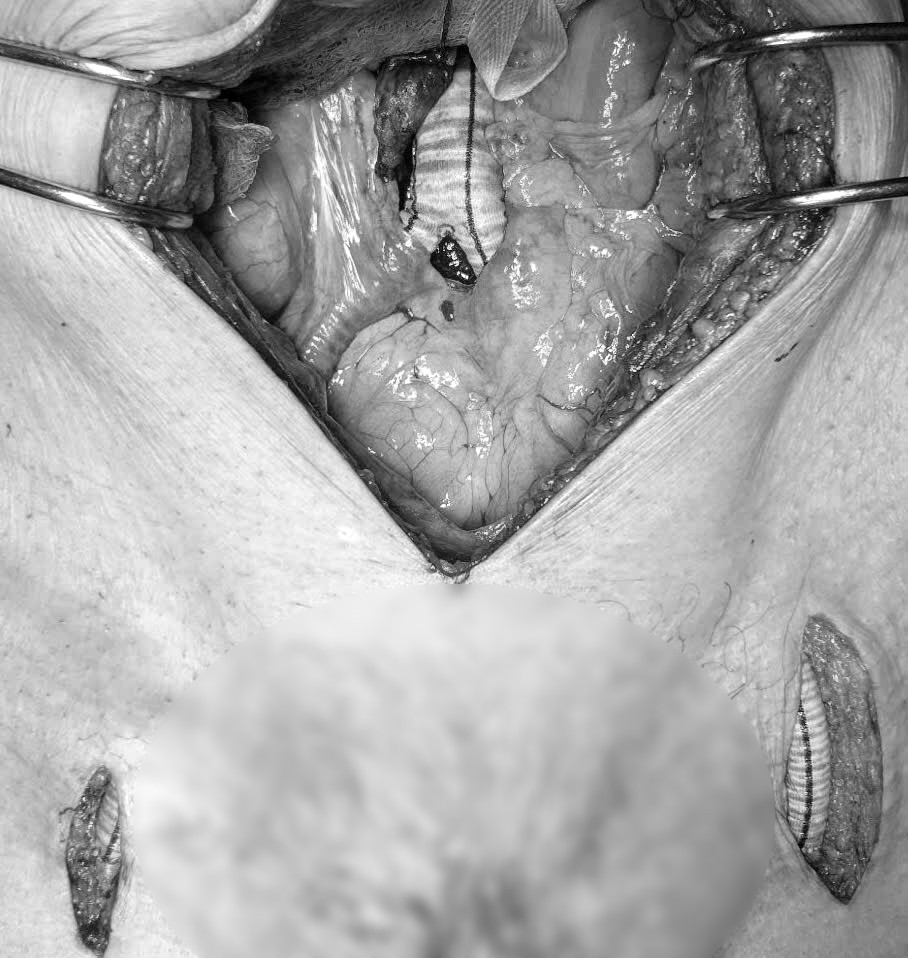

machchi1.jpg

Phẫu thuật bắc cầu mạch chi cho bệnh nhân 84 tuổi - Ảnh BVCC

Kíp mổ thực hiện ca phẫu thuật bắc cầu bằng mạch nhân tạo từ động mạch chủ bụng tới động mạch đùi hai bên và tiếp tục bắc cầu từ hai động mạch đùi để dẫn máu xuống cẳng chân, nhằm tái thông dòng máu nuôi chi dưới. Đây là kỹ thuật khó, đòi hỏi trình độ chuyên môn cao và sự phối hợp nhịp nhàng giữa các bác sĩ phẫu thuật mạch máu, gây mê hồi sức và chăm sóc hậu phẫu.

Sau 3 giờ căng thẳng, ca phẫu thuật đã thành công. Máu được tái thông, hai chân bệnh nhân hồng ấm trở lại, hết đau, cải thiện rõ rệt nguy cơ hoại tử. Cụ ông đã được cứu khỏi nguy cơ tàn phế, điều mà gia đình ông không dám hy vọng vì hoàn cảnh khó khăn.